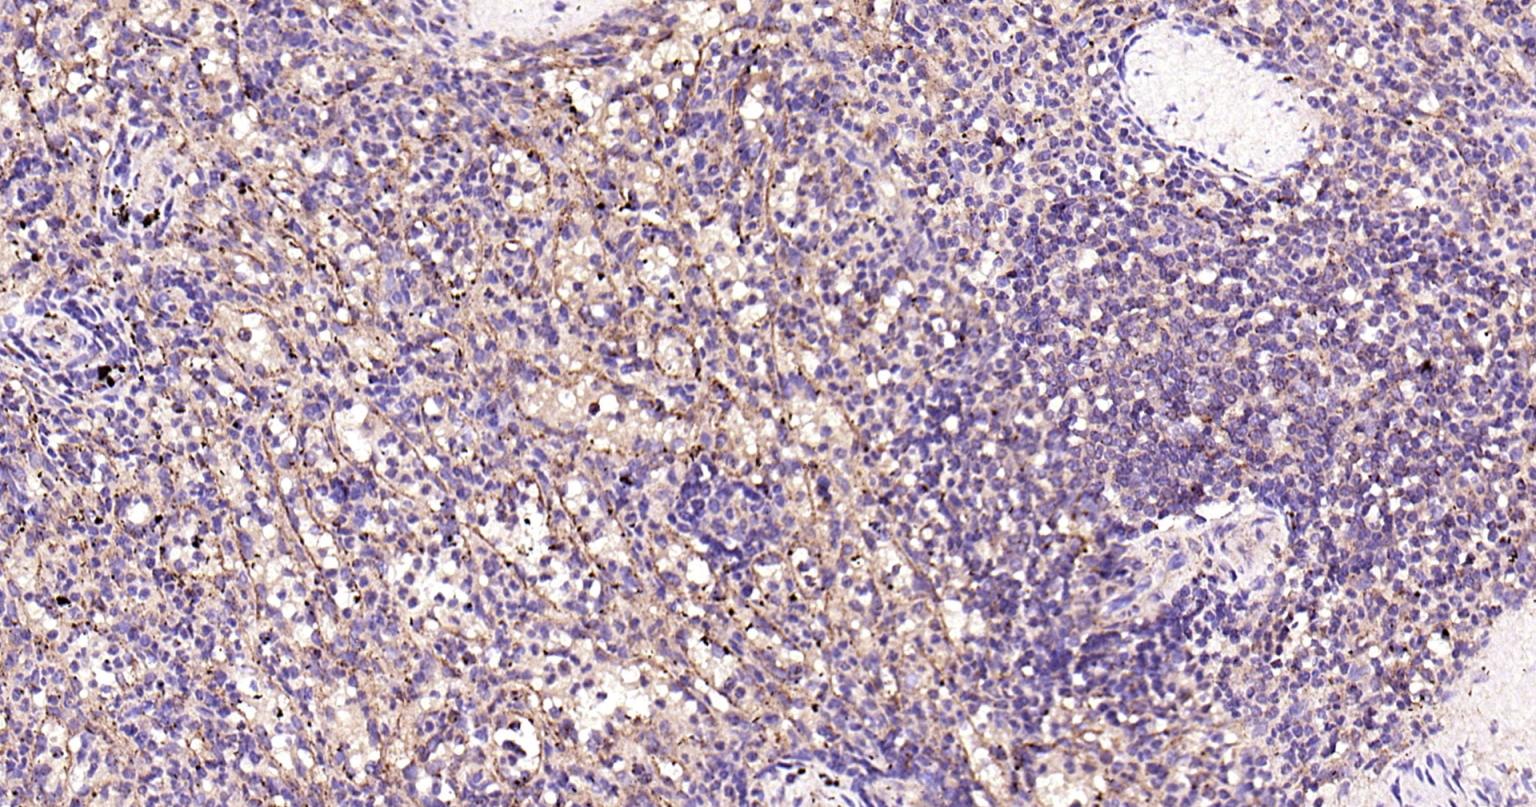

| IHC-P | Human | 1:100-500 | |